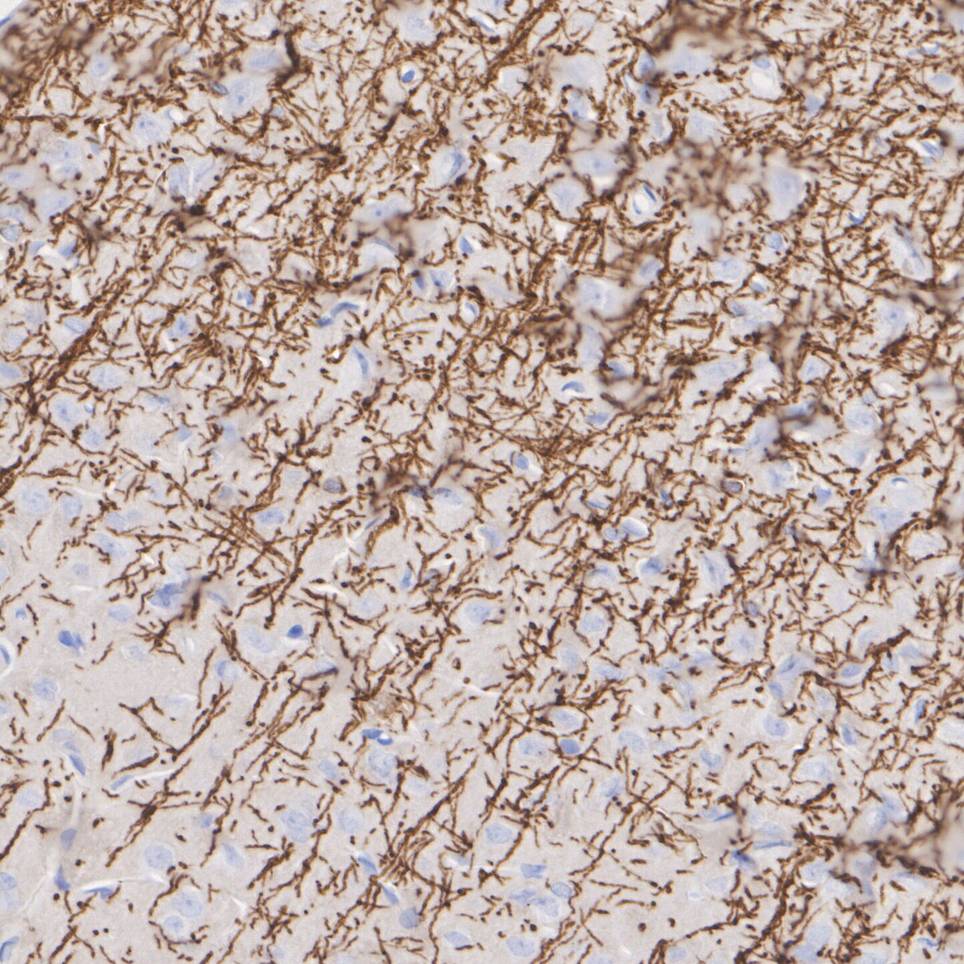

HA751212_4.jpg Fig4: Immunohistochemical analysis of paraffin-embedded human brain tissue with Rabbit anti-Myelin PLP antibody (HA751212) at 1/800 dilution.

The section was pre-treated using heat mediated antigen retrieval with Tris-EDTA buffer (pH 9.0) for 20 minutes. The tissues were blocked in 1% BSA for 20 minutes at room temperature, washed with ddH2O and PBS, and then probed with the primary antibody (HA751212) at 1/800 dilution for 1 hour at room temperature. The detection was performed using an HRP conjugated compact polymer system. DAB was used as the chromogen. Tissues were counterstained with hematoxylin and mounted with DPX.